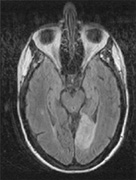

Fig. 5. Macula-splitting hemianopia. A 47-year-old man with AIDS and sudden onset of poor vision. A. Fields show complete left hemianopia. B. MRI shows lesion of right lateral occipital cortex, affecting distal optic radiations. Biopsy showed nonspecific encephalitis.

Fig. 6. Lesion of temporal optic radiation. Left superior quadrantanopia, respecting horizontal meridian (A), from infarct of right medial temporal lobe, in posterior cerebral artery territory (B). (From Rosen ES, Eustace P, Thompson HS, Cumming WJK [eds]: Neuro-Ophthalmology. London: Mosby, 1998.)